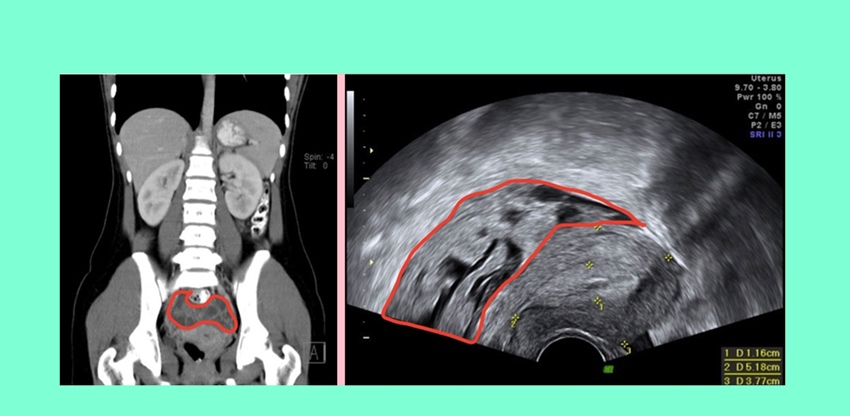

▲ 超音波影像(圖左)與電腦斷層影像(圖右)均顯示子宮後方有不規則腫塊。